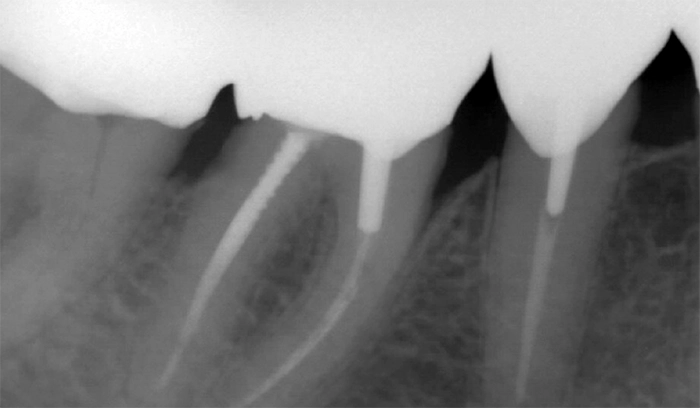

Réhabilitation globale

- Élément de liste #1

- Élément de liste #1

- Élément de liste #1

- Élément de liste #1